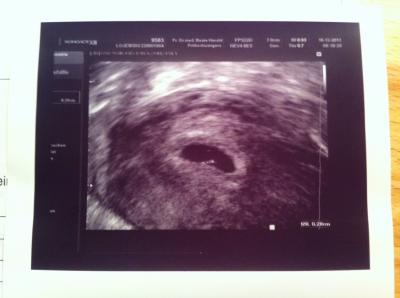

ich finde dein Bild sieht gut aus ..... irgendwie finde ich das auf meinem Bild so ne Kleine Fruchthöhle ist zu euren Bildern ... oder ???